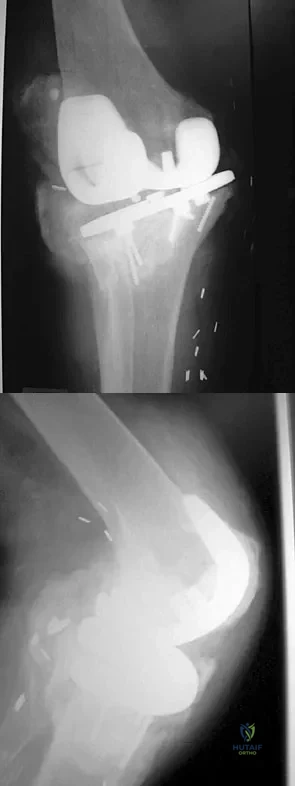

Figures 61a and 61b show the CT and MRI scans of a 40-year-old man who has hip pain. He undergoes total hip arthroplasty and curettage and cementation of the lesion as shown in Figure 61c. Histopathologic photomicrographs of the curettage specimen are shown in Figures 61d and 61e. What is the best course of treatment?

Explanation